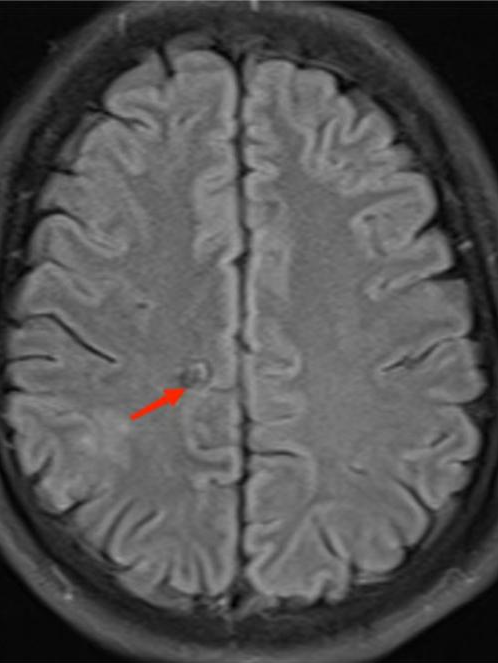

得到这条线索后,ICU 医生立即为李先生进行一系列脑部检查。最终,李先生头颅 MR 显示其脑内有寄生虫感染!明确诊断为脑囊虫病!